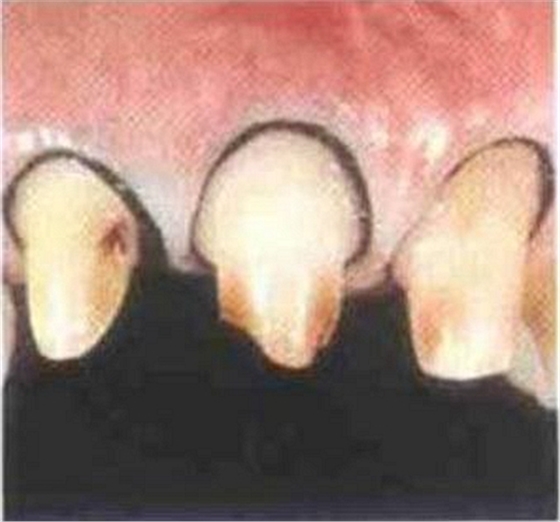

內(nèi)冠邊緣懸突是導(dǎo)致牙齦變色的"罪魁禍?zhǔn)?quot;

肩臺懸突易出現(xiàn)繼發(fā)齲

如今,全冠修復(fù)成為我們的主要修復(fù)形式。但人們?yōu)槠涿烙^考慮,大部分都采用齦下肩臺,將齦邊緣放入齦溝過深,而忽視了由于修復(fù)不當(dāng)引起的牙周損害的嚴(yán)重后果。 所以這里我只講齦下肩臺的預(yù)備深度。

冠邊緣的位置要放在一個適合的位置,齦溝的深度在患者口中會有很大不用,深度因人而異,尤其是存在牙齦或牙周炎癥的患者。其齦溝會有超過2mm的深度,絕大部分會小于1mm,冠邊緣不要損傷上皮性附著,這樣就會引起齦炎。

肩臺的外形應(yīng)與釉牙骨界相適應(yīng):注意備牙時上皮性附著在牙的不同側(cè)面的弧線各不相同。不要把肩臺備成平的,要與釉牙骨質(zhì)界的弧線相適應(yīng),只有嚴(yán)格遵守這一點才可以避免破壞上皮性附著而導(dǎo)致牙齦炎癥,進(jìn)而牙齦萎縮。